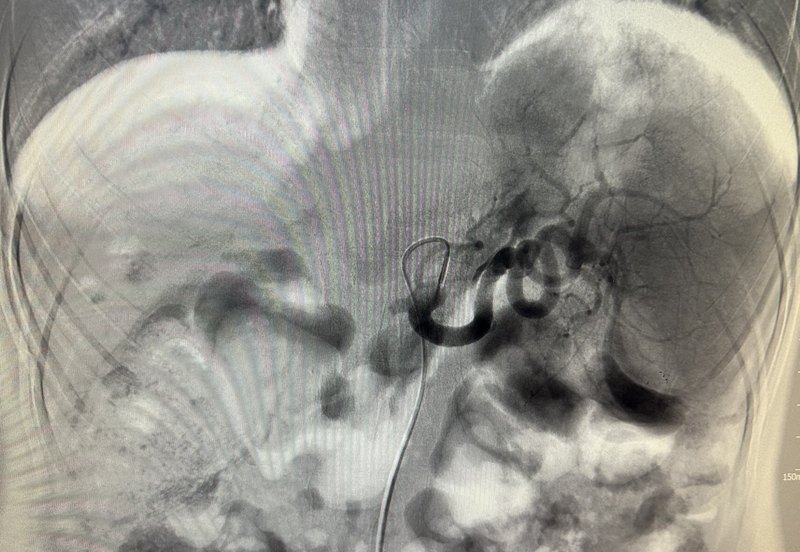

脾動脈主干栓塞序貫脾微波消融治療脾亢并消化道出血案例

患者男,52歲,乙肝肝硬化脾亢門脈高壓多年,近期反復(fù)消化道出血,內(nèi)鏡套扎治療效果不佳,患者拒絕tips治療,來我科求治,既往患者因肝癌破裂出血曾行tace及靶向治療。造影可見脾動脈增粗,肝動脈未見顯影,是脾動脈盜血導(dǎo)致。在脾動脈主干行彈簧圈栓塞限流治療。行脾微波消融治療,脾臟可見微波消融針。脾微波消融術(shù)中可見脾臟大片氣化。復(fù)查見脾臟大片無強化區(qū),為消融后改變。右肝腫瘤碘油栓塞加消融后局部完全滅活。術(shù)前血小板29-45之間波動。術(shù)后血小板76-102之間波動。術(shù)后患者無再發(fā)消化道出血,且體質(zhì)明顯改善,通過tace加微波消融完全滅活肝內(nèi)腫瘤,目前患者肝癌破裂出血兩年余,繼續(xù)密切隨診。點評:脾動脈主干栓塞序貫脾微波消融治療為肝癌并門脈高壓消化道出血患者提供多一個治療的思路,效果值得同道進一步驗證。